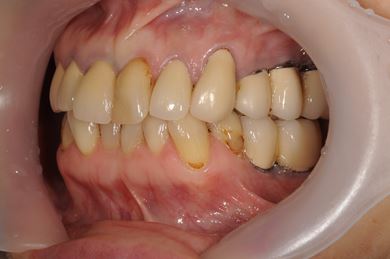

インプラントの症例写真 IMPLANT

骨再生スピードインプラント治療+セラミック治療

| 治療内容 | インプラント9本(抜歯即日スピードインプラント、サイナスリフト)、ハイブリッドセラミッククラウン12本(ハイブリッドセラミック用土台3本) | ||||||||||||||||||||||||||||||||

| 総治療費 | 4,157,213円 | ||||||||||||||||||||||||||||||||

| 治療期間 | 1年0ヶ月 |